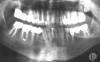

Bier Опубликовано 5 ноября, 2007 Поделиться Опубликовано 5 ноября, 2007 вы давайте уж всю панораму, а тоя смотрю там куча зубов с хроническим пульпитом, может элементарно другой зуб болит. Ссылка на комментарий

Hermit Опубликовано 5 ноября, 2007 Автор Поделиться Опубликовано 5 ноября, 2007 вы давайте уж всю панораму, а тоя смотрю там куча зубов с хроническим пульпитом, может элементарно другой зуб болит. Даю всю панораму (сдалана 3 недели назад) и рад буду услышать любые мнения о ней. Собственно говоря, я сделал неудачное протезирование в "элитной клинике" у одного "умельца", который выдавал себя за терапевта, ортопеда и хирурга. После трех безуспешных переделок коронок мне пришлось с ним расстаться. Был нарушен прикус, все было перекошено, коронки не подогнаны под шейки зубов, которые он взял под расточку не занявшись их предварительным перелечиванием. В результате многие из них стали болеть от перенагрузки. Сейчас занимаюсь перелечиваеним. Для начала удалил нижние ретенированные зубы мудрости. Теперь по очереди лечу зубы под коронками. В растоящее время перелечил нижнюю правую семерку, что отражено на снимке, нижнюю правую четверку и верхнюю левую пятерку (чего на снимке нет). Ссылка на комментарий

Bier Опубликовано 5 ноября, 2007 Поделиться Опубликовано 5 ноября, 2007 так наверху слева у вас может болеть и двойка и тройка и единица.Впрочем сейчас еще терапевты подойдут, мож что еще присоветуют. Ссылка на комментарий